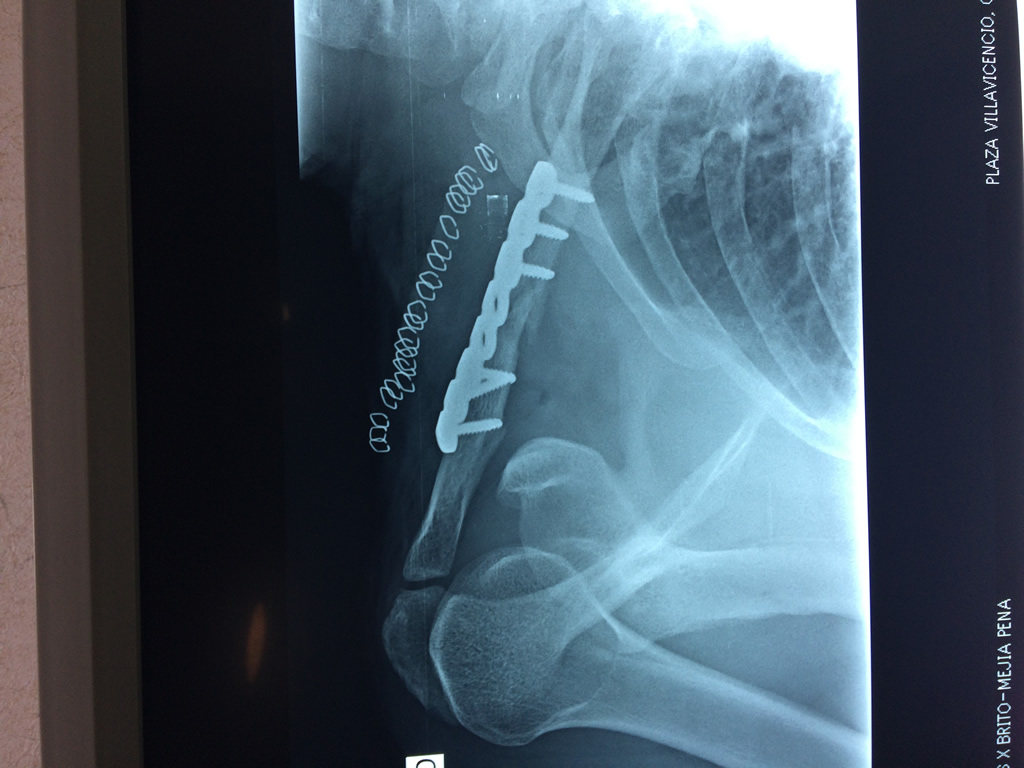

Cirugía de Fémur - Clavícula

La clavícula es un hueso largo, con forma de "S" itálica, situado en la parte anterosuperior del tórax. Junto con la escápula forman la cintura escapular. Se puede palpar por toda su longitud y se extiende del esternón al acromion de la escápula, siguiendo una dirección oblicua lateral y posterior.